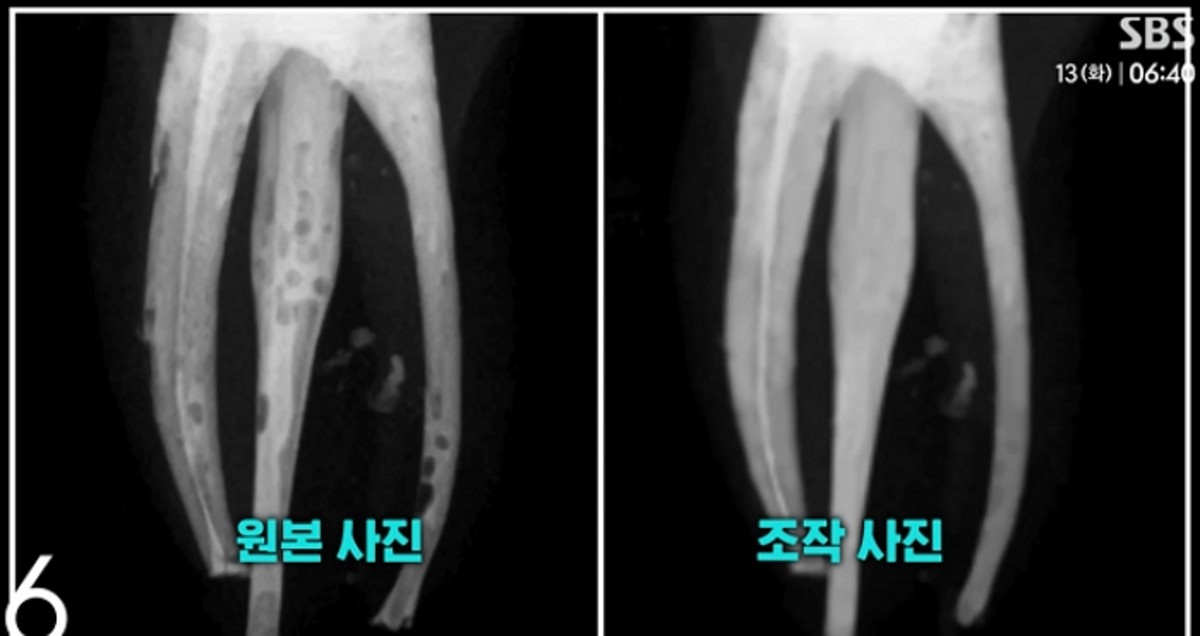

학생들은 신경 치료 과정에서 충전제 주입이 완전하지 않아 엑스레이 촬영 시 기포가 나타나자, 포토샵을 이용해 이를 제거하고 마치 완벽한 치료가 이뤄진 것처럼 결과물을 위조했습니다.

이번 부정행위에 관련된 학생 수는 총 34명에 달합니다. 전체 수강생 59명 중 과반수를 넘는 규모로, 이 중 29명은 직접 사진 조작에 가담했고 나머지 5명은 다른 학생의 조작된 결과물을 표절한 것으로 밝혀졌습니다.